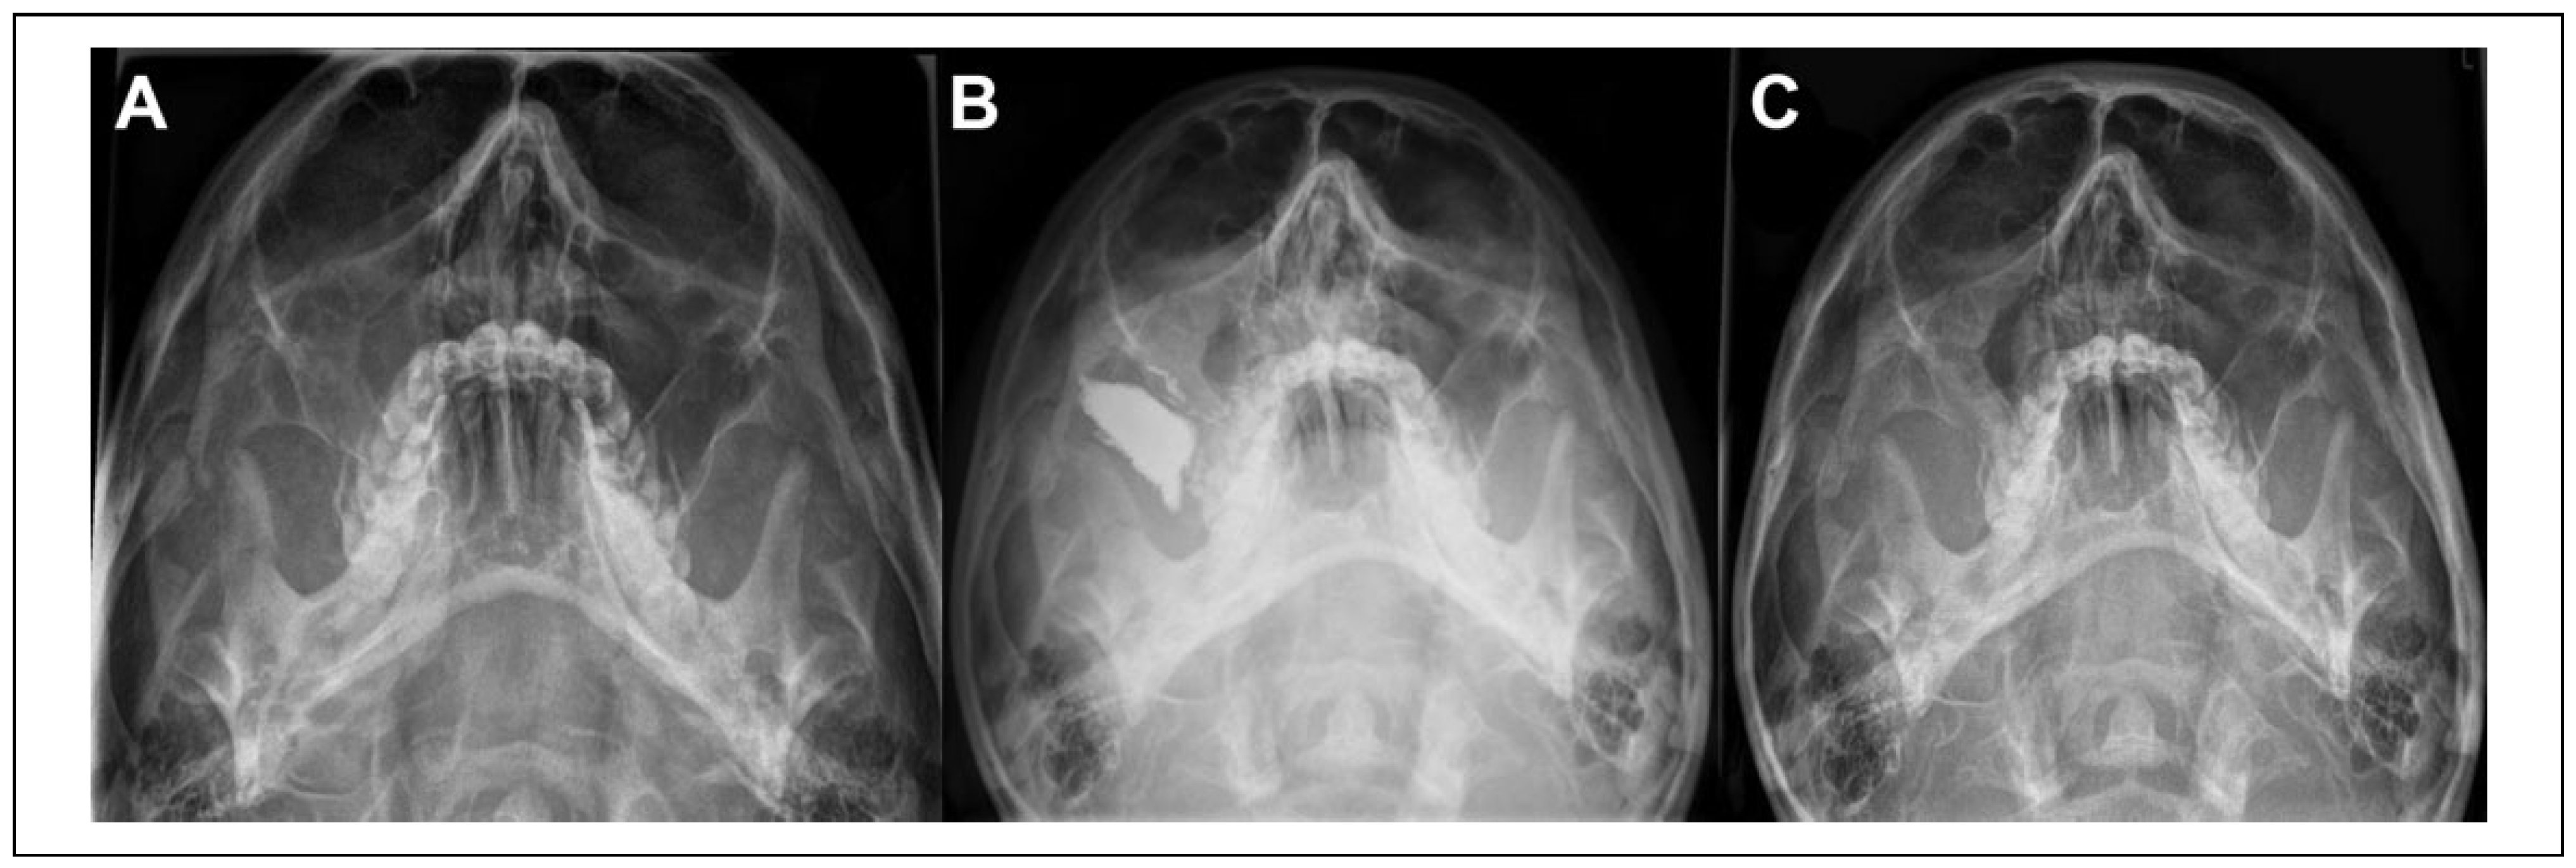

Seven patients required reoperation within 2 weeks of their primary procedure. We consider these to represent failure of the initial surgery. Five had undergone a “closed” approach with zygomatic elevation via a Gillies’ temporal approach and no fixation. Three required open reduction and internal fixation, while 2 refused open reduction. Both of these patients underwent a further elevation, one accepting the residual deformity while the other was treated with an antral pack to provide stability (Figure 1) and achieved a satisfactory outcome.

Figure 1. A, Result after primary surgery—note the depressed right zygomatic arch. B, Result immediately after secondary procedure with antral pack in situ. C, Final postoperative result after removal of antral pack.